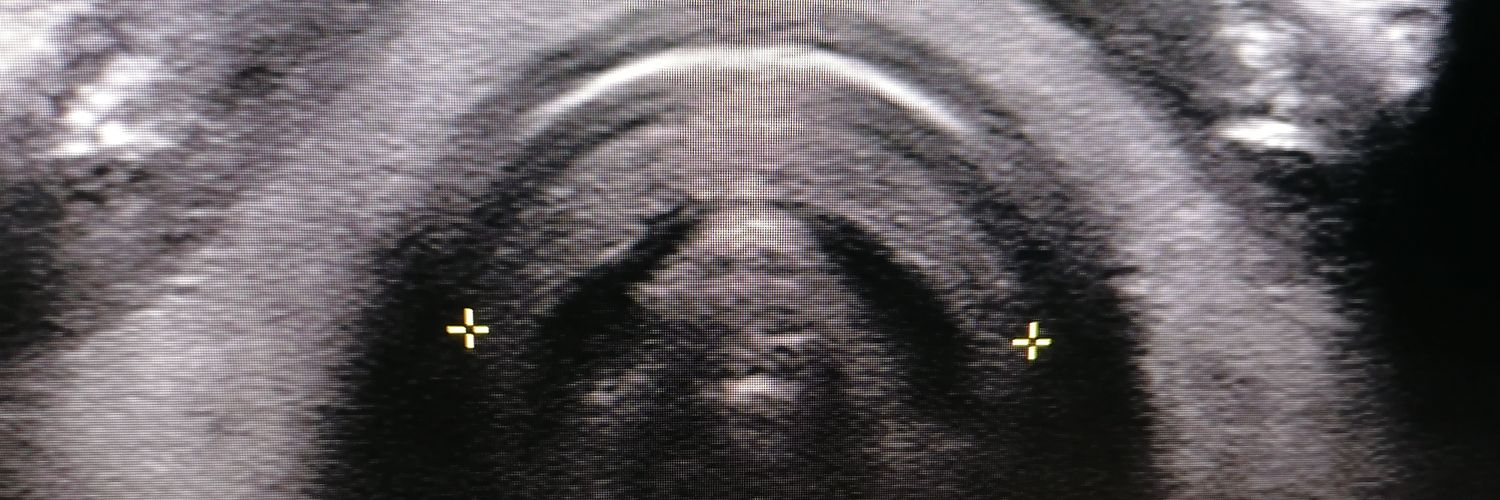

Another highlight of my #NIHR fellowship was getting to work with @HelenNewmanSLT on her #NIHR fellowship 🤩😍 A unique, if not surreal, experience using novel methods to understand the impact of #ultrasound artefact on upper airway assessment. Amazing work Helen.